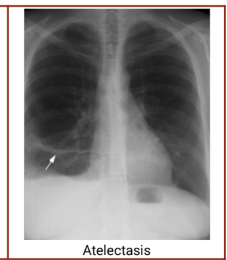

Chest radiography - Atelectasis